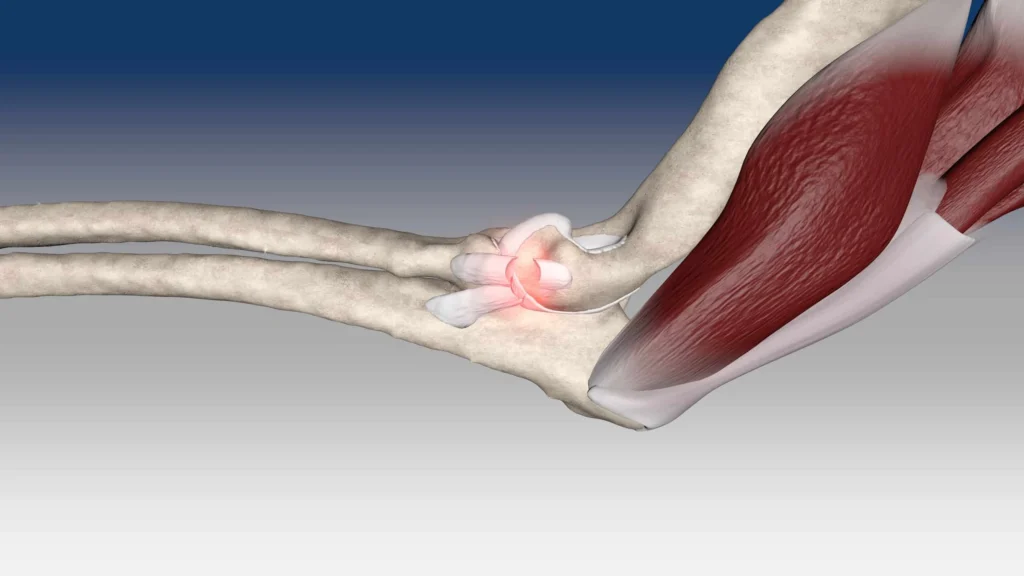

Elbow ligament reconstruction and stabilization surgery is a specialized procedure designed to repair or reconstruct damaged ligaments in the elbow joint. Ligaments are crucial for maintaining the stability of the elbow, allowing for proper movement and function. Injuries to these ligaments, particularly the ulnar collateral ligament (UCL) in athletes or those involved in repetitive overhead motions, can lead to pain, instability, and loss of function. Elbow ligament reconstruction and stabilization are effective solutions to restore stability, relieve pain, and allow for a return to regular activities, including sports.

Elbow ligament reconstruction involves the repair or replacement of a damaged ligament, typically the UCL, which is located on the inner side of the elbow. The UCL is essential for stabilizing the elbow, particularly during activities that involve throwing or repetitive overhead motions.

In cases where the ligament is torn or severely damaged, a surgical procedure is performed to either repair or reconstruct the ligament using graft tissue from the patient’s own body or a donor (autograft or allograft). In some cases, other ligaments and soft tissues around the elbow may also be repaired or stabilized to improve overall joint function and stability.

Ulnar Collateral Ligament (UCL) Injuries: UCL tears or instability are common among athletes, especially in baseball players and other sports involving overhead throwing motions. UCL injuries can result in pain, instability, and decreased performance, requiring surgical intervention to restore the ligament’s function.